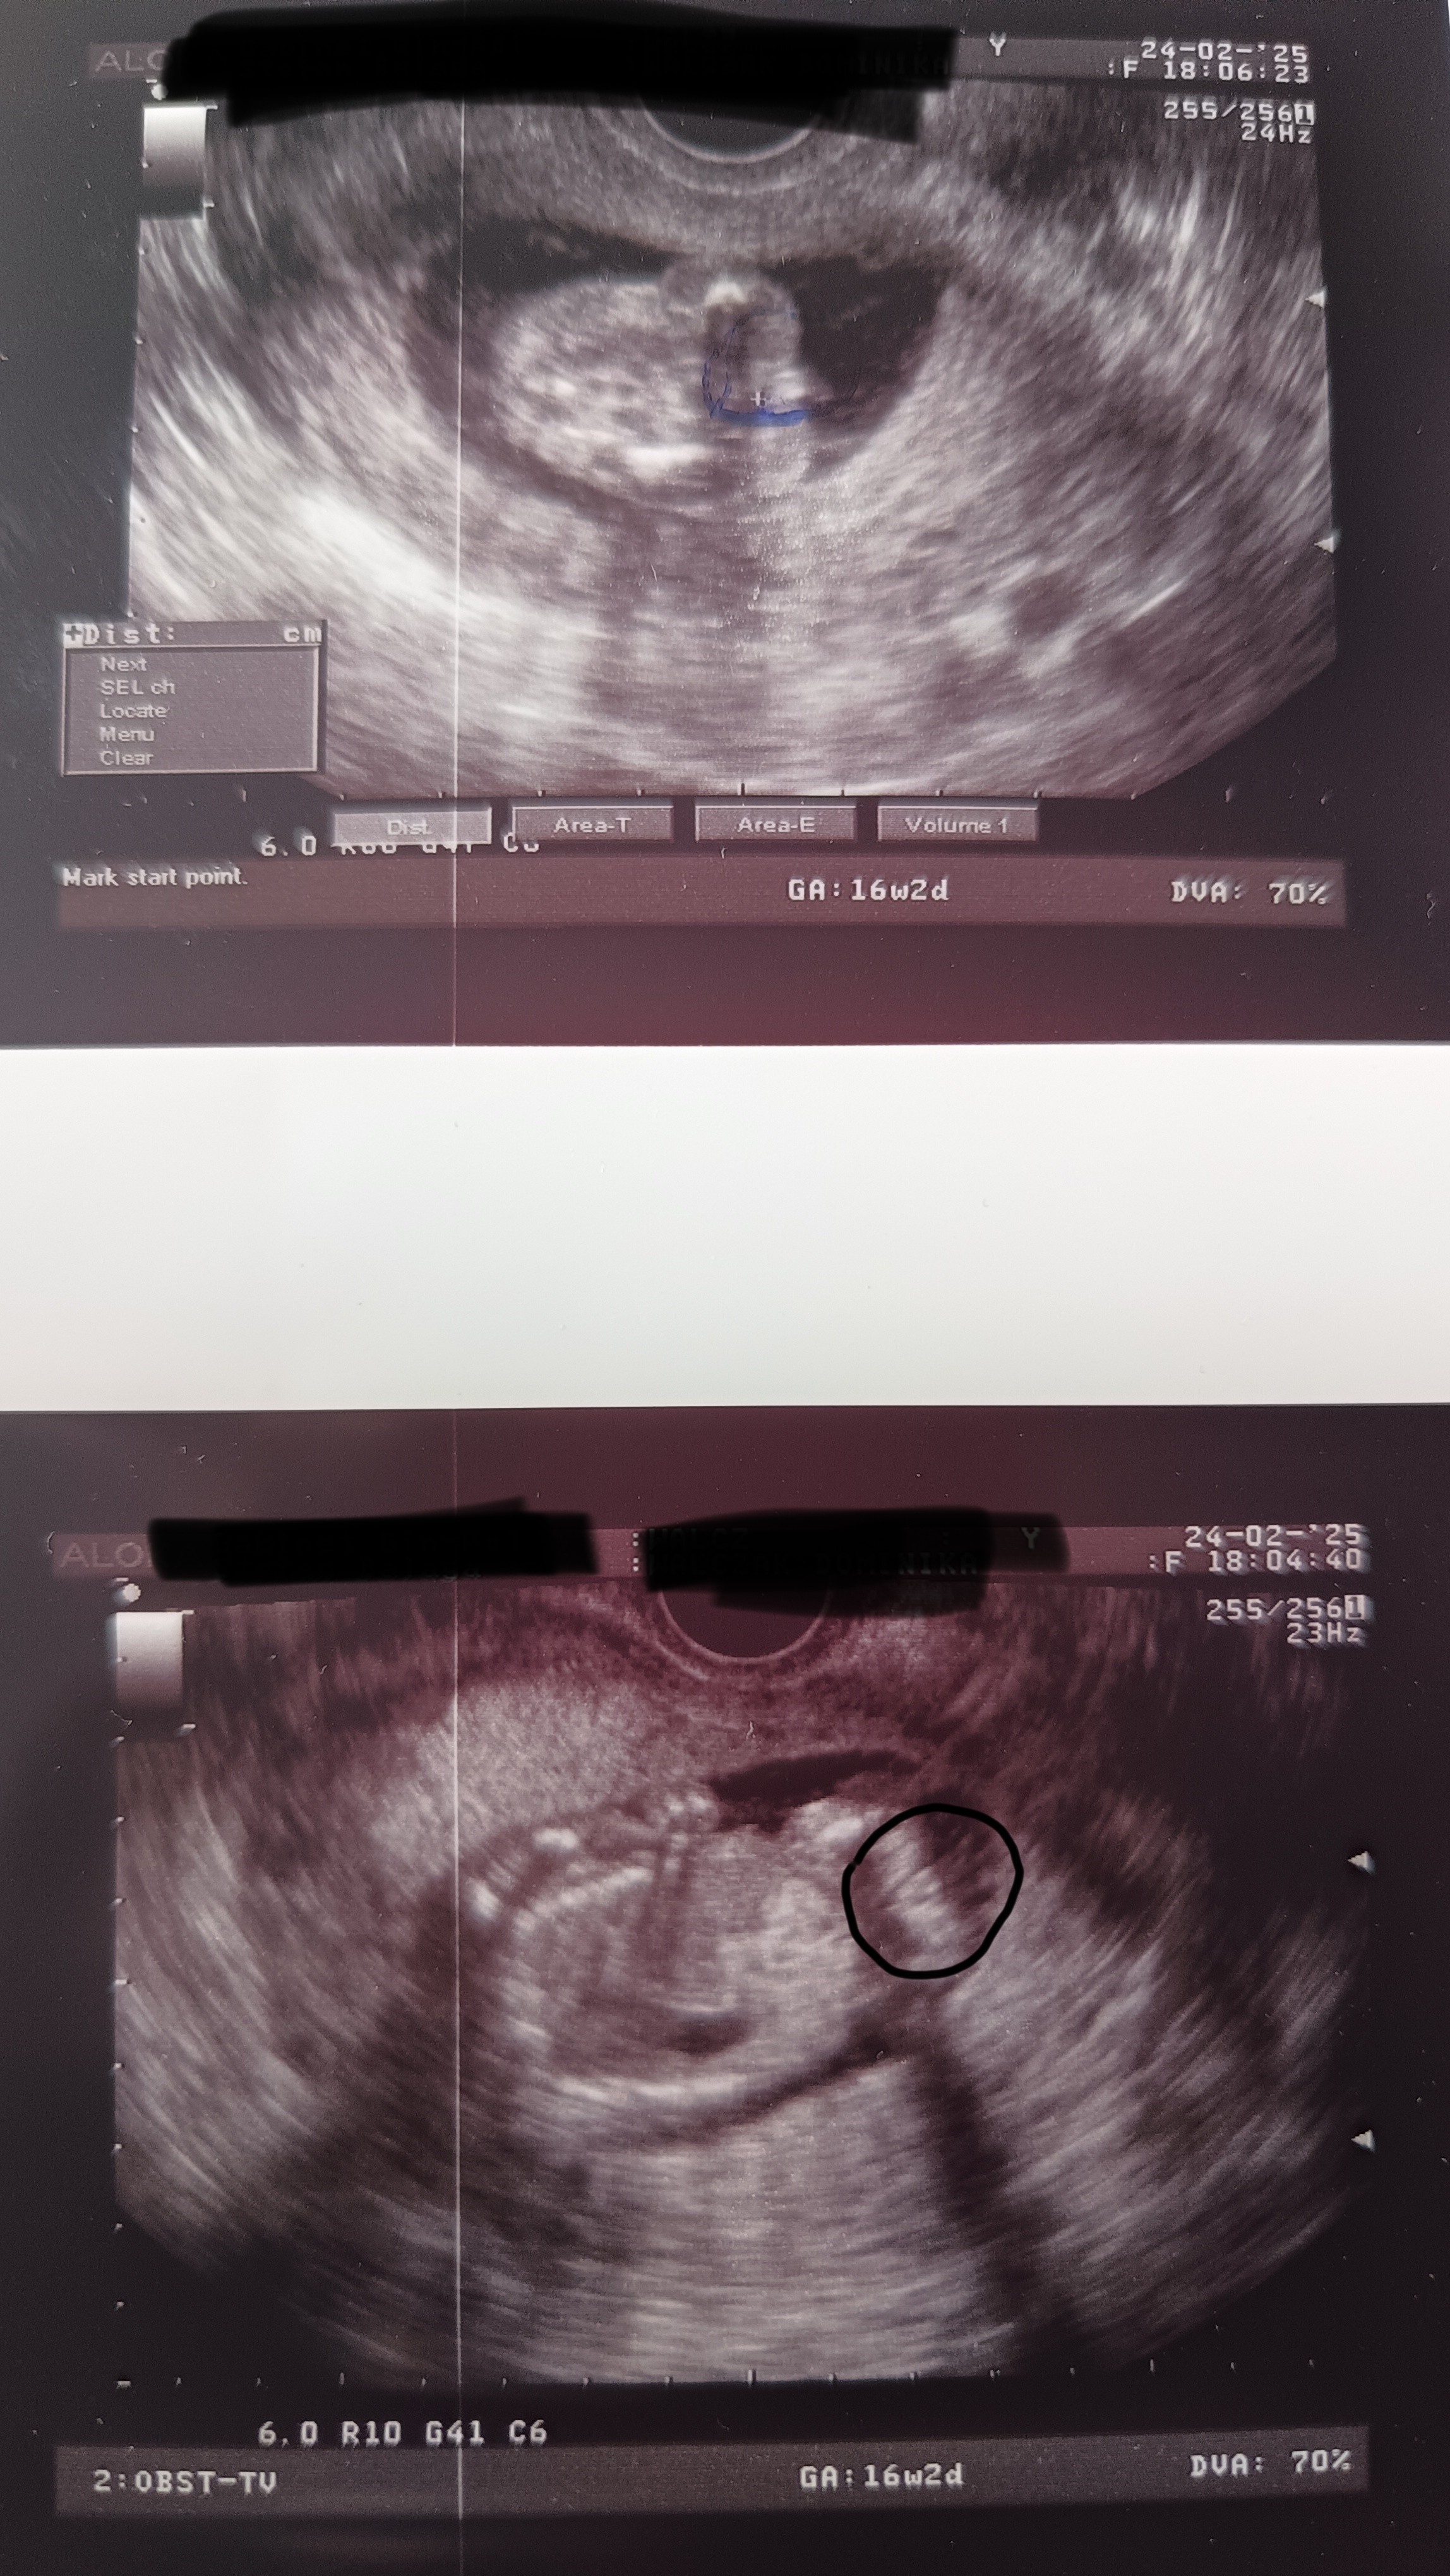

Tak, powiedziałabym, że taki obraz „hamburgera” to dziewczynka. U nas były podobne 3 kreseczki.Hej wiem że jest tutaj sporo doświadczonych mam, czy któraś z Was jest w stanie mi powiedzieć czy na tych zdjęciach USG faktycznie widać dziewczynkę ?

Tak, powiedziałabym, że taki obraz „hamburgera” to dziewczynka. U nas były podobne 3 kreseczki.

Chyba dziewczynkaHej wiem że jest tutaj sporo doświadczonych mam, czy któraś z Was jest w stanie mi powiedzieć czy na tych zdjęciach USG faktycznie widać dziewczynkę ?

No ja mam potwierdzone już na pewno że dziewczynka, wczorajsze prenatalne potwierdziłyChyba dziewczynka